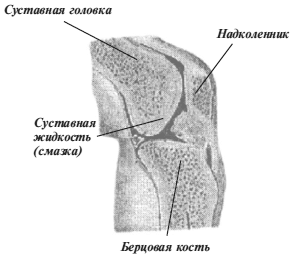

Суставная Жидкость и Головка Сустава: Обзор и Здоровье